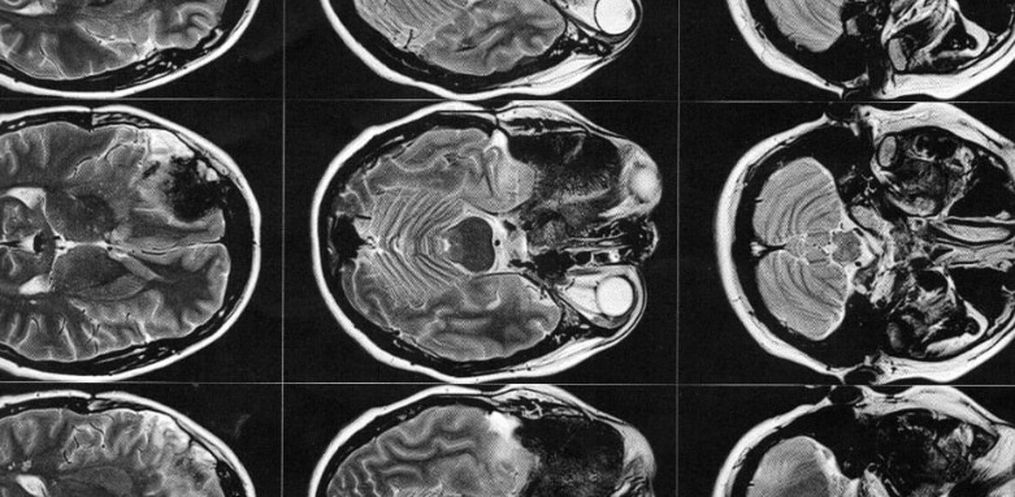

1 ano e 7 meses após o nascimento da Manuela (hoje com quase 4 anos), mais precisamente em dezembro de 2018, Gisele foi em busca de um neurocirurgião que estivesse apto a realizar a cirurgia. Optou-se por um médico da região, pela facilidade de locomoção. Por sua vez, por meio de exames de imagem, este médico a diagnosticou com um meningioma intraósseo (tumor cerebral benigno que se origina nas células das meninges).

Em fevereiro de 2019 passou pela primeira cirurgia de retirada do meningioma. Tudo correu bem, sem sequelas. No entanto, teve uma parte do osso (medindo 7,5 x 6 x 2 cm) em sua cabeça que teve que ser retirado e não pôde ser colocado novamente, pois o tumor estava enraizado naquela região, e eram grandes as chances de reincidência. Após a cirurgia, foi enviado para análise a amostra do tumor, que confirmou, de fato, se tratar de um tumor benigno.

Então este médico solicitou exames de imagem (ressonância magnética e tomografia) para avaliar a situação, os quais foi constatado que o meningioma ainda está ali, e que continua empurrando o olho e se expandindo para outras áreas. Trata-se de um meningioma gigante (medindo 6 x 6,6 x 6 cm), que está localizado na placa do assoalho da fossa média e anterior.